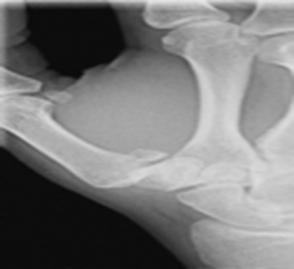

Luxación del semilunar

Es el hueso del carpo más luxado. El mecanismo es por caída sobre la palma de la mano con desviación ventral. Signo del “dorso de tenedor”, es común la lesión del nervio mediano, el cual pasa, anatómicamente, por delante del semilunar. (Ver Figura 61)